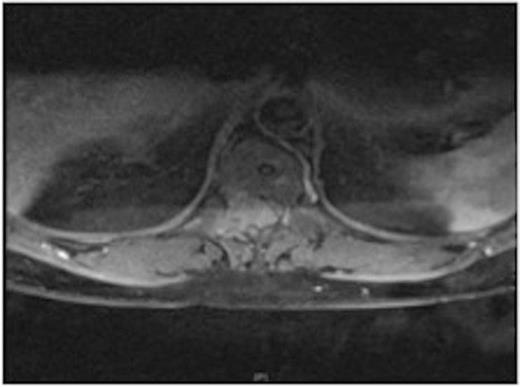

A one-year history of lower back pain, which was initially thought to be due to his liver metastasis, was investigated further with a full spine MRI scan. The scan revealed a large T10-11 extra-dural tumour with erosion of the T12 pedicle and extension into the soft tissue of the back. As a result of this discovery, the patient was referred for radiotherapy. Prior to commencement of this the oncologist requested a neurosurgical opinion from us.

MRI showing the T10-11 extra-dural tumour with erosion of the T12 pedicle

Due to the low-grade nature of the tumour and the spinal cord compression the advantages and disadvantages of surgery versus radiotherapy were discussed with the patient who then agreed to have the tumour surgically removed.